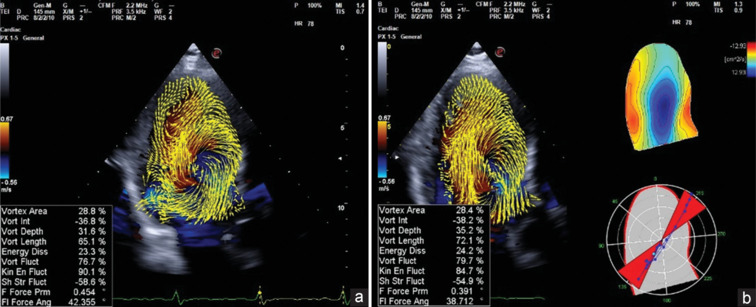

Methods and results: A group of 23 highly trained athletes was studied using two-dimensional standard and deformation echo parameters and vortex examination. A dedicated software (HyperDoppler-ESAOTE) defined geometrical and dynamic vortex parameters (area, length, depth, energy dissipation [ED], vorticity fluctuation, and kinetic energy fluctuation). The data obtained were compared with a group of 26 active nonathletes and a group of 23 normal subjects. Body mass index differed among the three groups, with higher values in normal subjects (normal = 27.2 ± 5.7; active = 22.9 ± 2.6; triathletes = 22.1 ± 1.8; P = 0.01). Indexed left ventricle mass was significantly higher in triathletes (triathletes = 96.9 ± 14.9; active = 87.6 ± 15; normal = 79.5 ± 15.7; P = 0.003) as twist (triathletes = 12.3 ± 3.9; active = 9.8 ± 3.7; normal = 8.1 ± 3.1; P = 0.001), expressing a supernormal apical reserve. Diastolic function was normal in both groups. In the presence of normal geometrical vortex data, vortex energetic parameters were significantly higher in triathletes (ED = 1.10 ± 0.41, P < 0.001; vorticity fluctuation = 0.89 ± 0.04, P < 0.001; kinetic energy fluctuation = 1.01 ± 0.08, P < 0.001).

Conclusions: Vortex analysis complements the morphological remodeling of the athlete's heart. It can contribute to defining the effects of training intensity and energy consumption. Future research will focus on potential modifications in different sports.